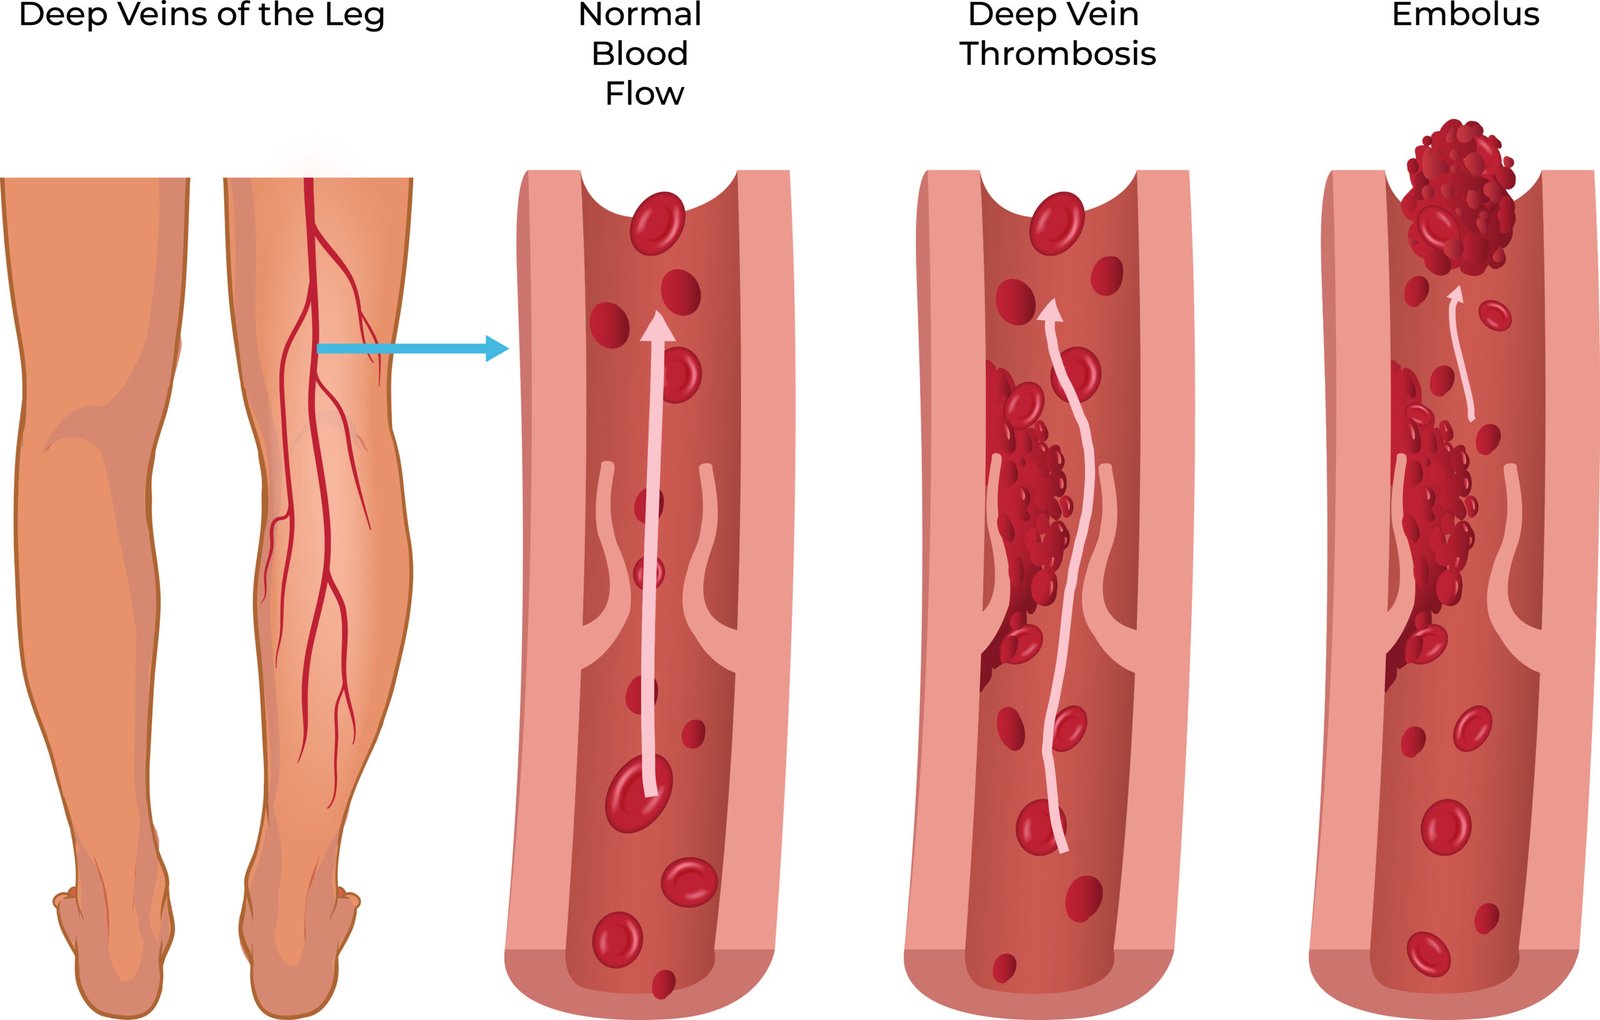

Stop the Clot: Understanding Deep Vein Thrombosis

Deep Vein Thrombosis (DVT) is a serious condition that can lead to life-threatening complications li…